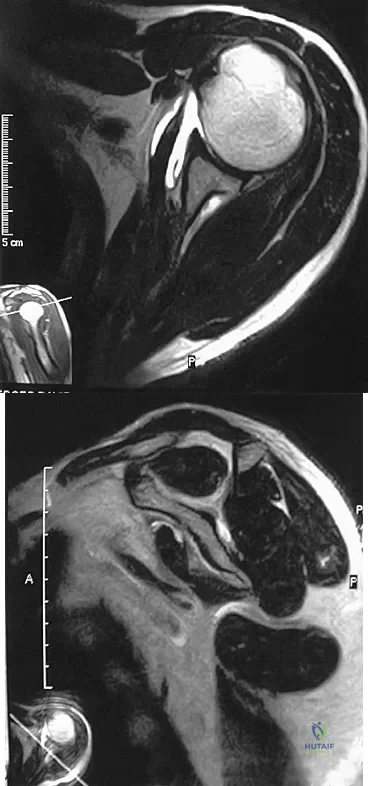

A 54-year man has left shoulder pain and weakness after falling while skiing 4 months ago. Examination reveals full range of motion passively, but he has a positive abdominal compression test and weakness with the lift-off test. External rotation strength with the arm at the side and strength with the arm abducted and internally rotated are normal. MRI scans are shown in Figures 1a and 1b. Treatment should consist of